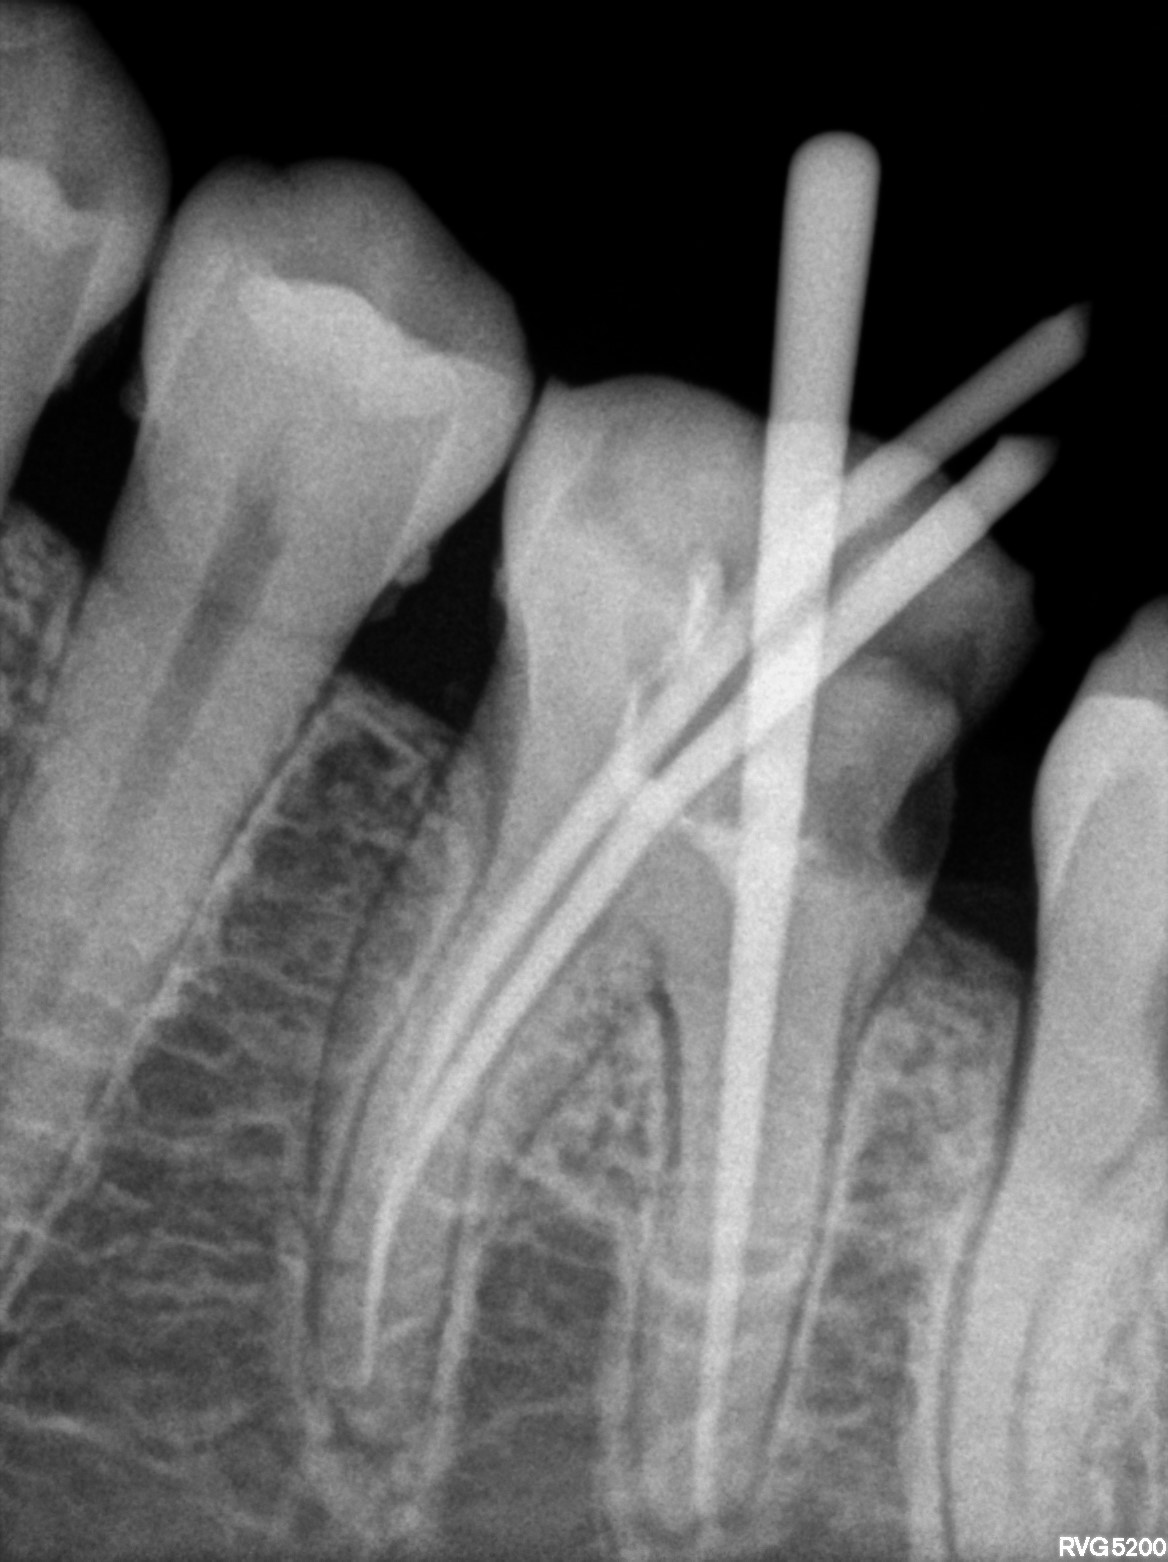

Dental Radiographs FHIR: DocumentReference · LOINC 24641-7

xray_1767429752_0.jpg

24641-7